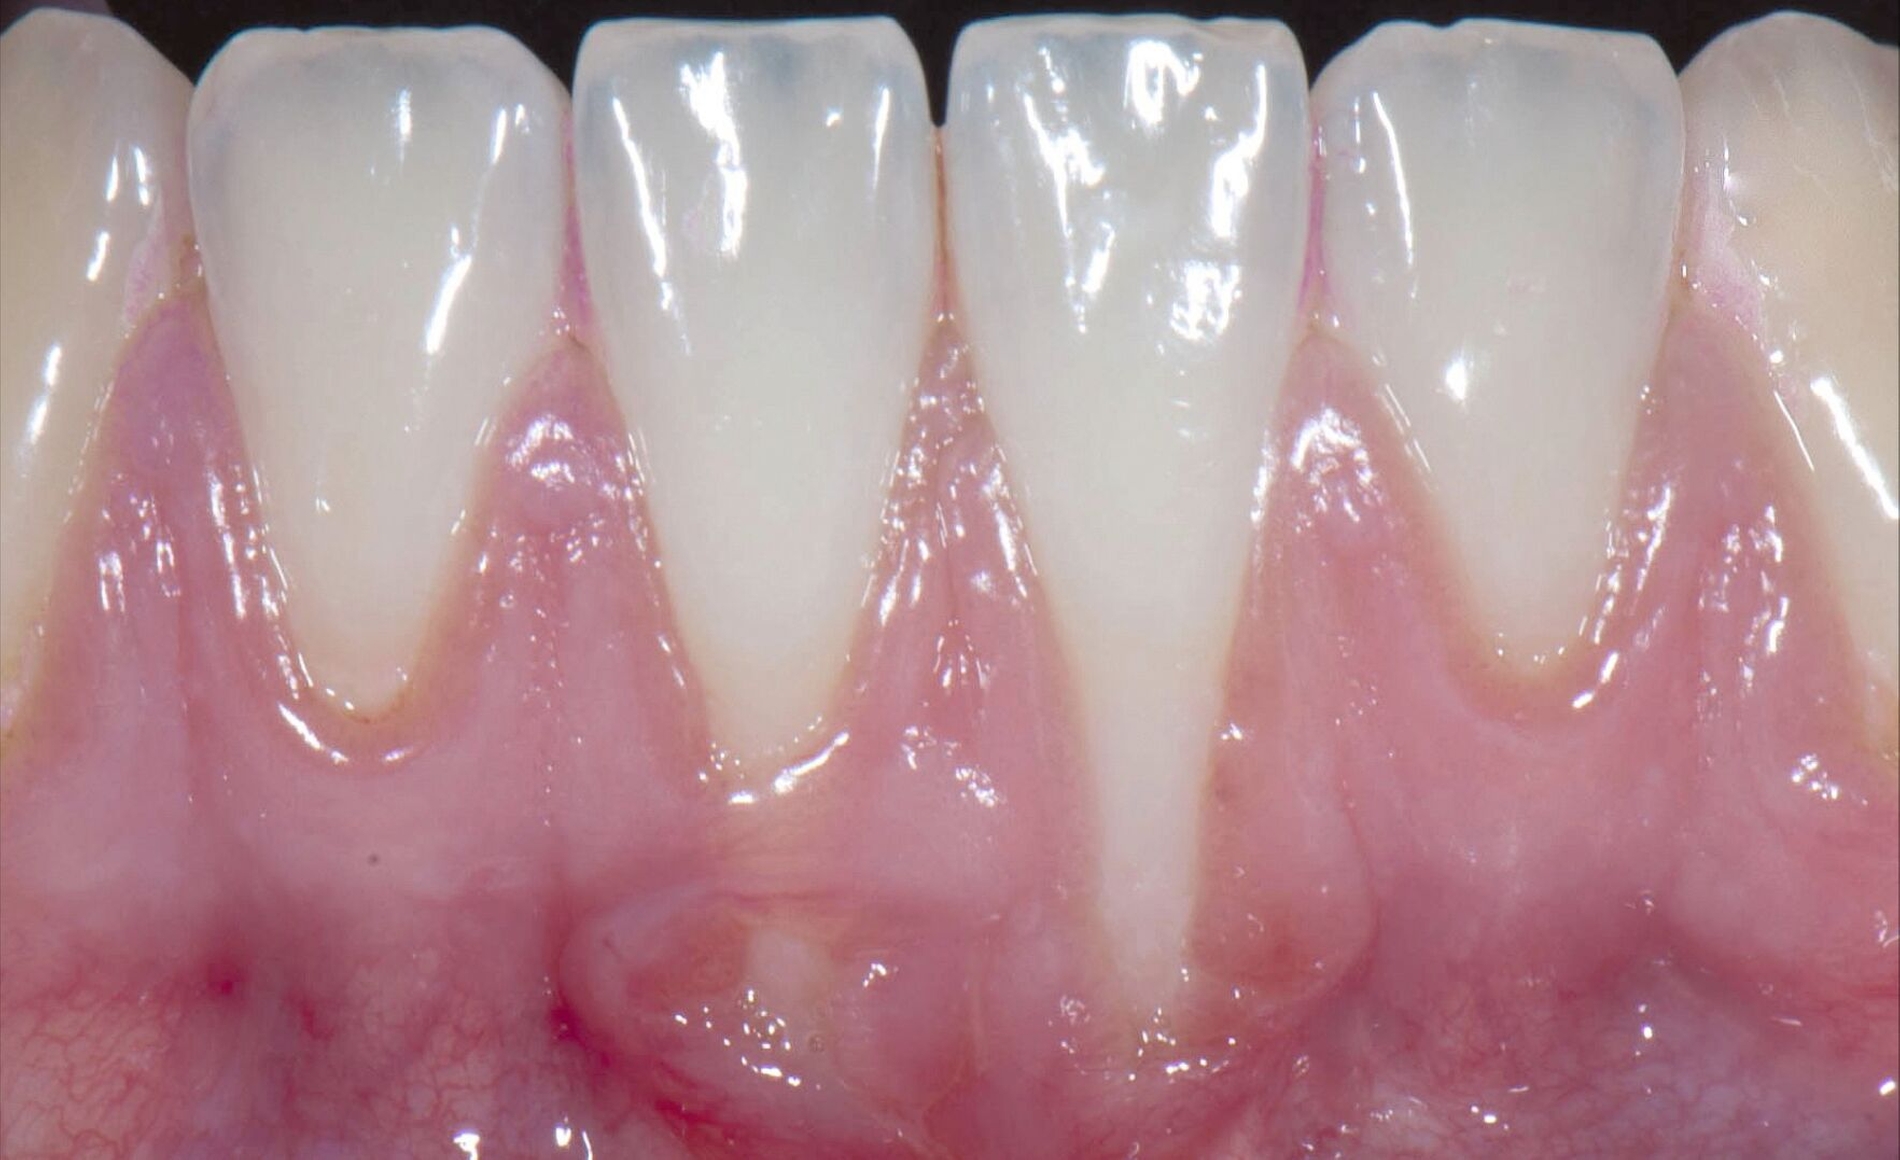

Indikationen für plastisch-parodontalchirurgische Verfahren zur Deckung der freiliegenden Wurzeloberfläche bei gingivalen Rezessionen können eine beeinträchtigte Ästhetik, der Schutz vor Wurzelkaries oder nicht-kariösen zervikalen Läsionen, aber auch die Beseitigung einer Dentinhypersensitivität (DH) sein. Diese ist definiert als kurzer oder transienter scharfer Schmerz der von freiliegendem Dentin ausgeht, typischerweise als Reaktion auf mechanische, thermische, chemische oder osmotische Stimuli. Basierend auf aktuellen Metaanalysen liegt die geschätzte Prävalenz bei 11,5 Prozent.

Die vorliegende Untersuchung zeigt, dass eine parodontalchirurgische Wurzeldeckung bei mehr als zwei Dritteln der Patienten zu Beseitigung ihrer Dentinhypersensitivität führen konnte. Dabei waren sowohl das Ausmaß der Rezessionsreduktion als auch der prozentualen Wurzeldeckung mit einer Beseitigung der DH assoziiert. Dementsprechend kann ein plastisch-parodontalchirurgischer Eingriff zur Rezessionsdeckung nach Beseitigung möglicher ätiologischer Faktoren für die Rezessionsentstehung zur Behandlung einer DH empfohlen werden.